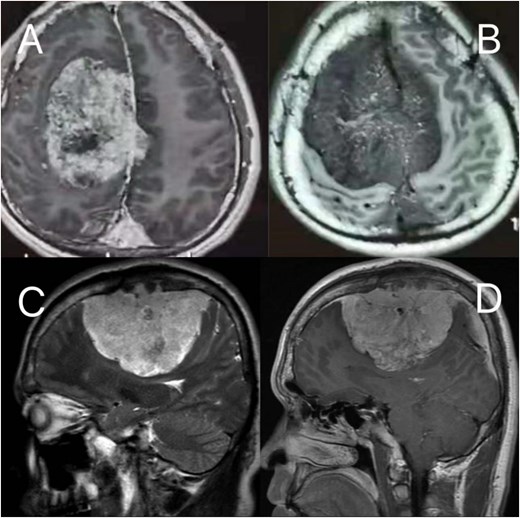

Preoperative MRI: (A, B) axial post-contrast T2-weighted and T1-weighted, respectively (C, D) sagittal position post-contrast T2-weighted and T1-weighted, respectively. The MRI findings describe a lesion in the right frontoparietal region adjacent to the superior sagittal sinus, measuring ~8.6 × 8.2 × 6.9 cm. The lesion demonstrates long T1 and T2 signal characteristics and exhibits marked heterogeneous enhancement on contrast-enhanced scans. It encircles the superior sagittal sinus and extends across the cerebral falx to the contralateral side, with multiple tortuous flow-void vascular shadows observed within and around the lesion. The mass is broadly attached to the adjacent calvarium, invading the diploic layer of the skull. Posteriorly, it extends along the superior sagittal sinus to the origin of the left transverse sinus. Compression of adjacent brain parenchyma results in irregular narrowing of the lateral ventricle and leftward shift of midline structures. Additionally, the cerebellar tonsils appear pointed and inferiorly displaced.